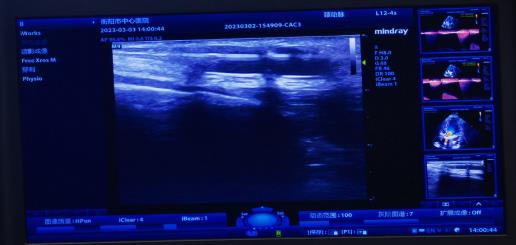

腎內(nèi)科通訊員黃佩君報道:來自衡陽縣的謝奶奶2年前因尿毒癥開始行維持性血液透析維持生命,1周前內(nèi)瘺流量明顯下降,不能滿足透析需要,慕名來到我院腎內(nèi)科就診。彩超檢查提示內(nèi)瘺口至內(nèi)瘺口近心端有約2.5cm管腔狹窄,經(jīng)綜合評估后,腎內(nèi)科陳鐵領(lǐng)副主任、彩超室王勝利副主任醫(yī)師、腎內(nèi)科王靜醫(yī)師給予患者實施彩超引導(dǎo)下動靜脈內(nèi)瘺狹窄球囊擴(kuò)張術(shù),短短20分鐘便完成手術(shù),術(shù)后患者內(nèi)瘺震顫明顯,流量大幅增加。

動靜脈內(nèi)瘺球囊擴(kuò)張術(shù)(PTA),通俗地講就是在超聲引導(dǎo)下,通過經(jīng)皮穿刺血管,置入導(dǎo)絲,沿導(dǎo)絲將高壓球囊送至血管狹窄/栓塞病變處,然后使用壓力泵打開球囊,將狹窄/栓塞的病變擴(kuò)張開的過程。它的優(yōu)勢非常明顯,不僅手術(shù)創(chuàng)面?。o切口,僅為一穿刺點),失血少,安全有效,可反復(fù)進(jìn)行,術(shù)后即可使用,不需中心靜脈靜脈導(dǎo)管過渡,患者舒適無痛苦,最重要的節(jié)省保護(hù)了患者的血管資源,可確保透析順利進(jìn)行。是目前動靜脈內(nèi)瘺狹窄/栓塞首選治療方法。